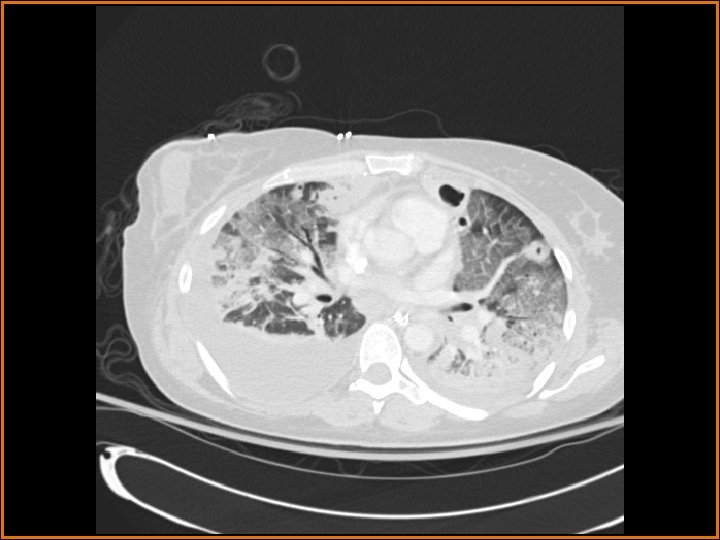

Findings and Differentials CT Findings: Multiple bilateral peripheral nodular opacities are seen, many of which are fed by arterial branches. Some of the nodules are cavitary. Diffuse bilateral ground glass opacities are seen with air bronchograms. The large lucency projecting over the right hemidiaphragm on the plain film corresponds to a pleural air collection that is directly contiguous with one of the cavities. Differential Diagnosis: • Multiple cavitary metastases • Septic Emboli

Discussion The differential diagnosis of cavitary nodules includes cavitary metastases, septic emboli, fungal infections, rheumatoid nodules, Wegener's granulomatosis, and rheumatoid nodules, among others. In this patient with fever, an infectious or inflammatory etiology is at the top of the differential. Correlation of the history with the imaging findings supports the diagnosis of septic emboli. Septic emboli usually manifest as multiple, bilateral peripheral opacities which may or may not cavitate. Often, the emboli will be in different stages of cavitation. Demonstration of a feeding vessel into the nodules indicates the hematogenous etiology of this process (although hematogenous metastases and a small-vessel vasculitis could certainly exhibit this feature also). Septic emboli may lead to pulmonary infarctions, which are seen as wedge-shaped opacities abutting the pleural surface, with the apex of the triangle pointing away from the pleura. The periphery of the infarct can enhance, but the center usually does not. Distinguishing infarcts from pneumonia is made easier when a vessel can be seen terminating at the apex of the infarcted region. (CONTINUED ON NEXT SLIDE)

Discussion (Continued) In this patient, the large right anteroinferior pleural air collection is contiguous with one of the cavities (as seen on the second CT image) and represents a bronchopleural fistula. Etiologies of bronchopleural fistulas include necrotizing infection, active TB, irradiation, tumor in a bronchial margin, etc. If the bronchopleural fistula is large, a persistent pneumothorax with or without contralateral mediastinal shift may be present. In this case, a septic embolus had eroded into the pleural space, creating the lucent collection projecting over the right hemithorax on the plain films. Finally, the ground glass opacities represented pneumonia in this patient.